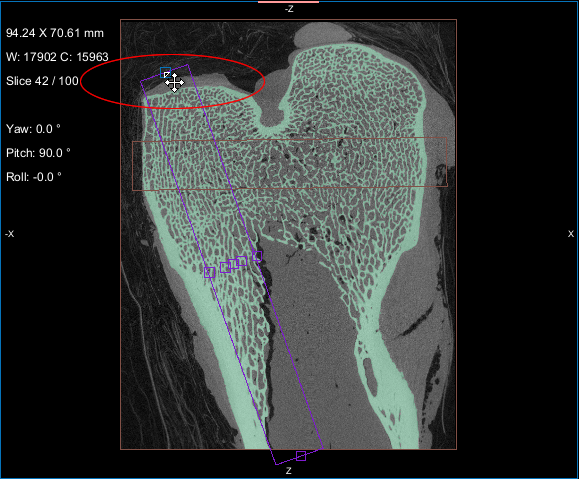

- Create a box that either entirely or partially encloses the region of interest as follows:

- Click the Box button in the Shapes panel.

A new Box shape appears in the Data Properties and Settings panel. Click the Eye icon to show the box in the workspace views.

- Adjust the box in the 2D and/or 3D views of the region of interest, as required.

You can resize and rotate the box, as well as change its position with the available control points (see Editing Shapes).

- Choose the box that encloses the area that you want to include in your analysis in the Area box drop-down menu.